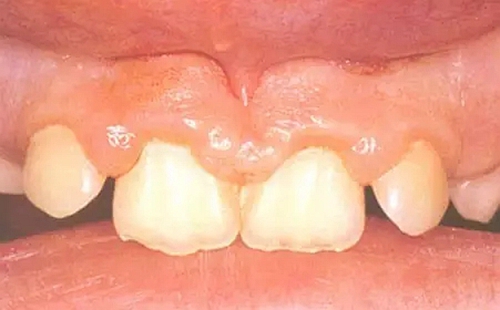

牙周組織病——牙齦炎

牙齦炎——指發(fā)生在牙齦組織的的急、慢性炎癥,常見表現(xiàn)為牙齦出血,紅腫脹痛,有可能向深層發(fā)展導(dǎo)致牙周炎。談起牙齦炎,很多家長認(rèn)為成年人很常見,卻忽略了寶寶也是易患牙齦炎的群體。

兒童牙齦炎的易患因素:

(1) 兒童牙齦上皮薄、角化差、脆弱,受細(xì)菌感染或者外傷刺激后易發(fā)生炎癥;

(2) 乳牙牙齒近牙頸部1/3隆起,牙頸部明顯縮窄,齦溝處易積存食物殘渣;

(3) 萌出期暫時性牙列不齊可以導(dǎo)致牙垢堆積,牙石附著,食物嵌塞;

(4) 兒童口腔清潔困難,唾液粘稠。